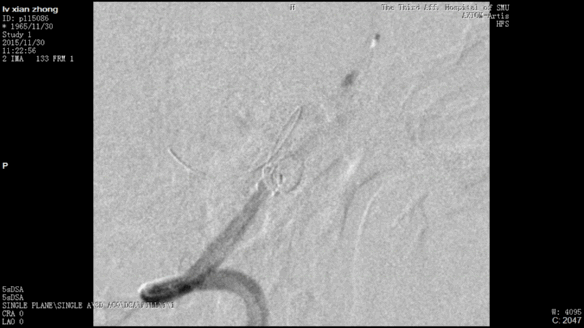

今天为大家分享的是“强生医疗CNV-神经介入专栏”第二十五期,由南方医科大学第三附属医院神经外科主任黄理金教授带来的“Enterprise支架辅助栓塞动脉瘤的优势”精彩讲课视频及PPT,欢迎观看。文章仅代表作者个人观点,如有不同见解,欢迎同道斧正!